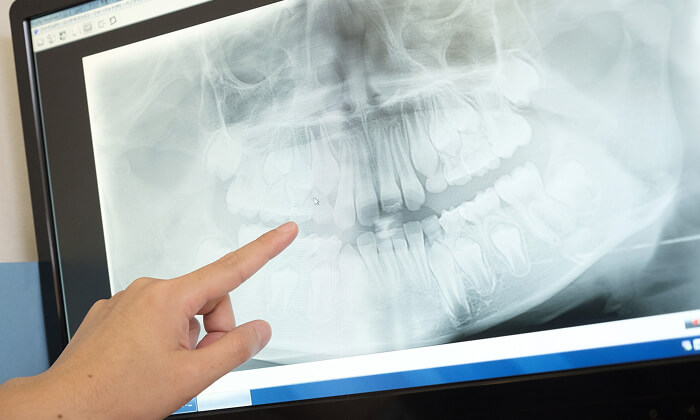

正確な診断

歯周ポケット測定やレントゲン・CT解析など、多角的な検査で歯周病の進行度と原因を正確に把握します。患者さま一人ひとりに最適な治療計画を立て、根拠ある治療につなげます。

精密検査

実際にお口の中の状態をチェックしていきます。レントゲン撮影にて歯や骨の検査を行い、虫歯や治療痕のチェック、歯周病検査などの各種検査を行い、総合的な診断を下します。